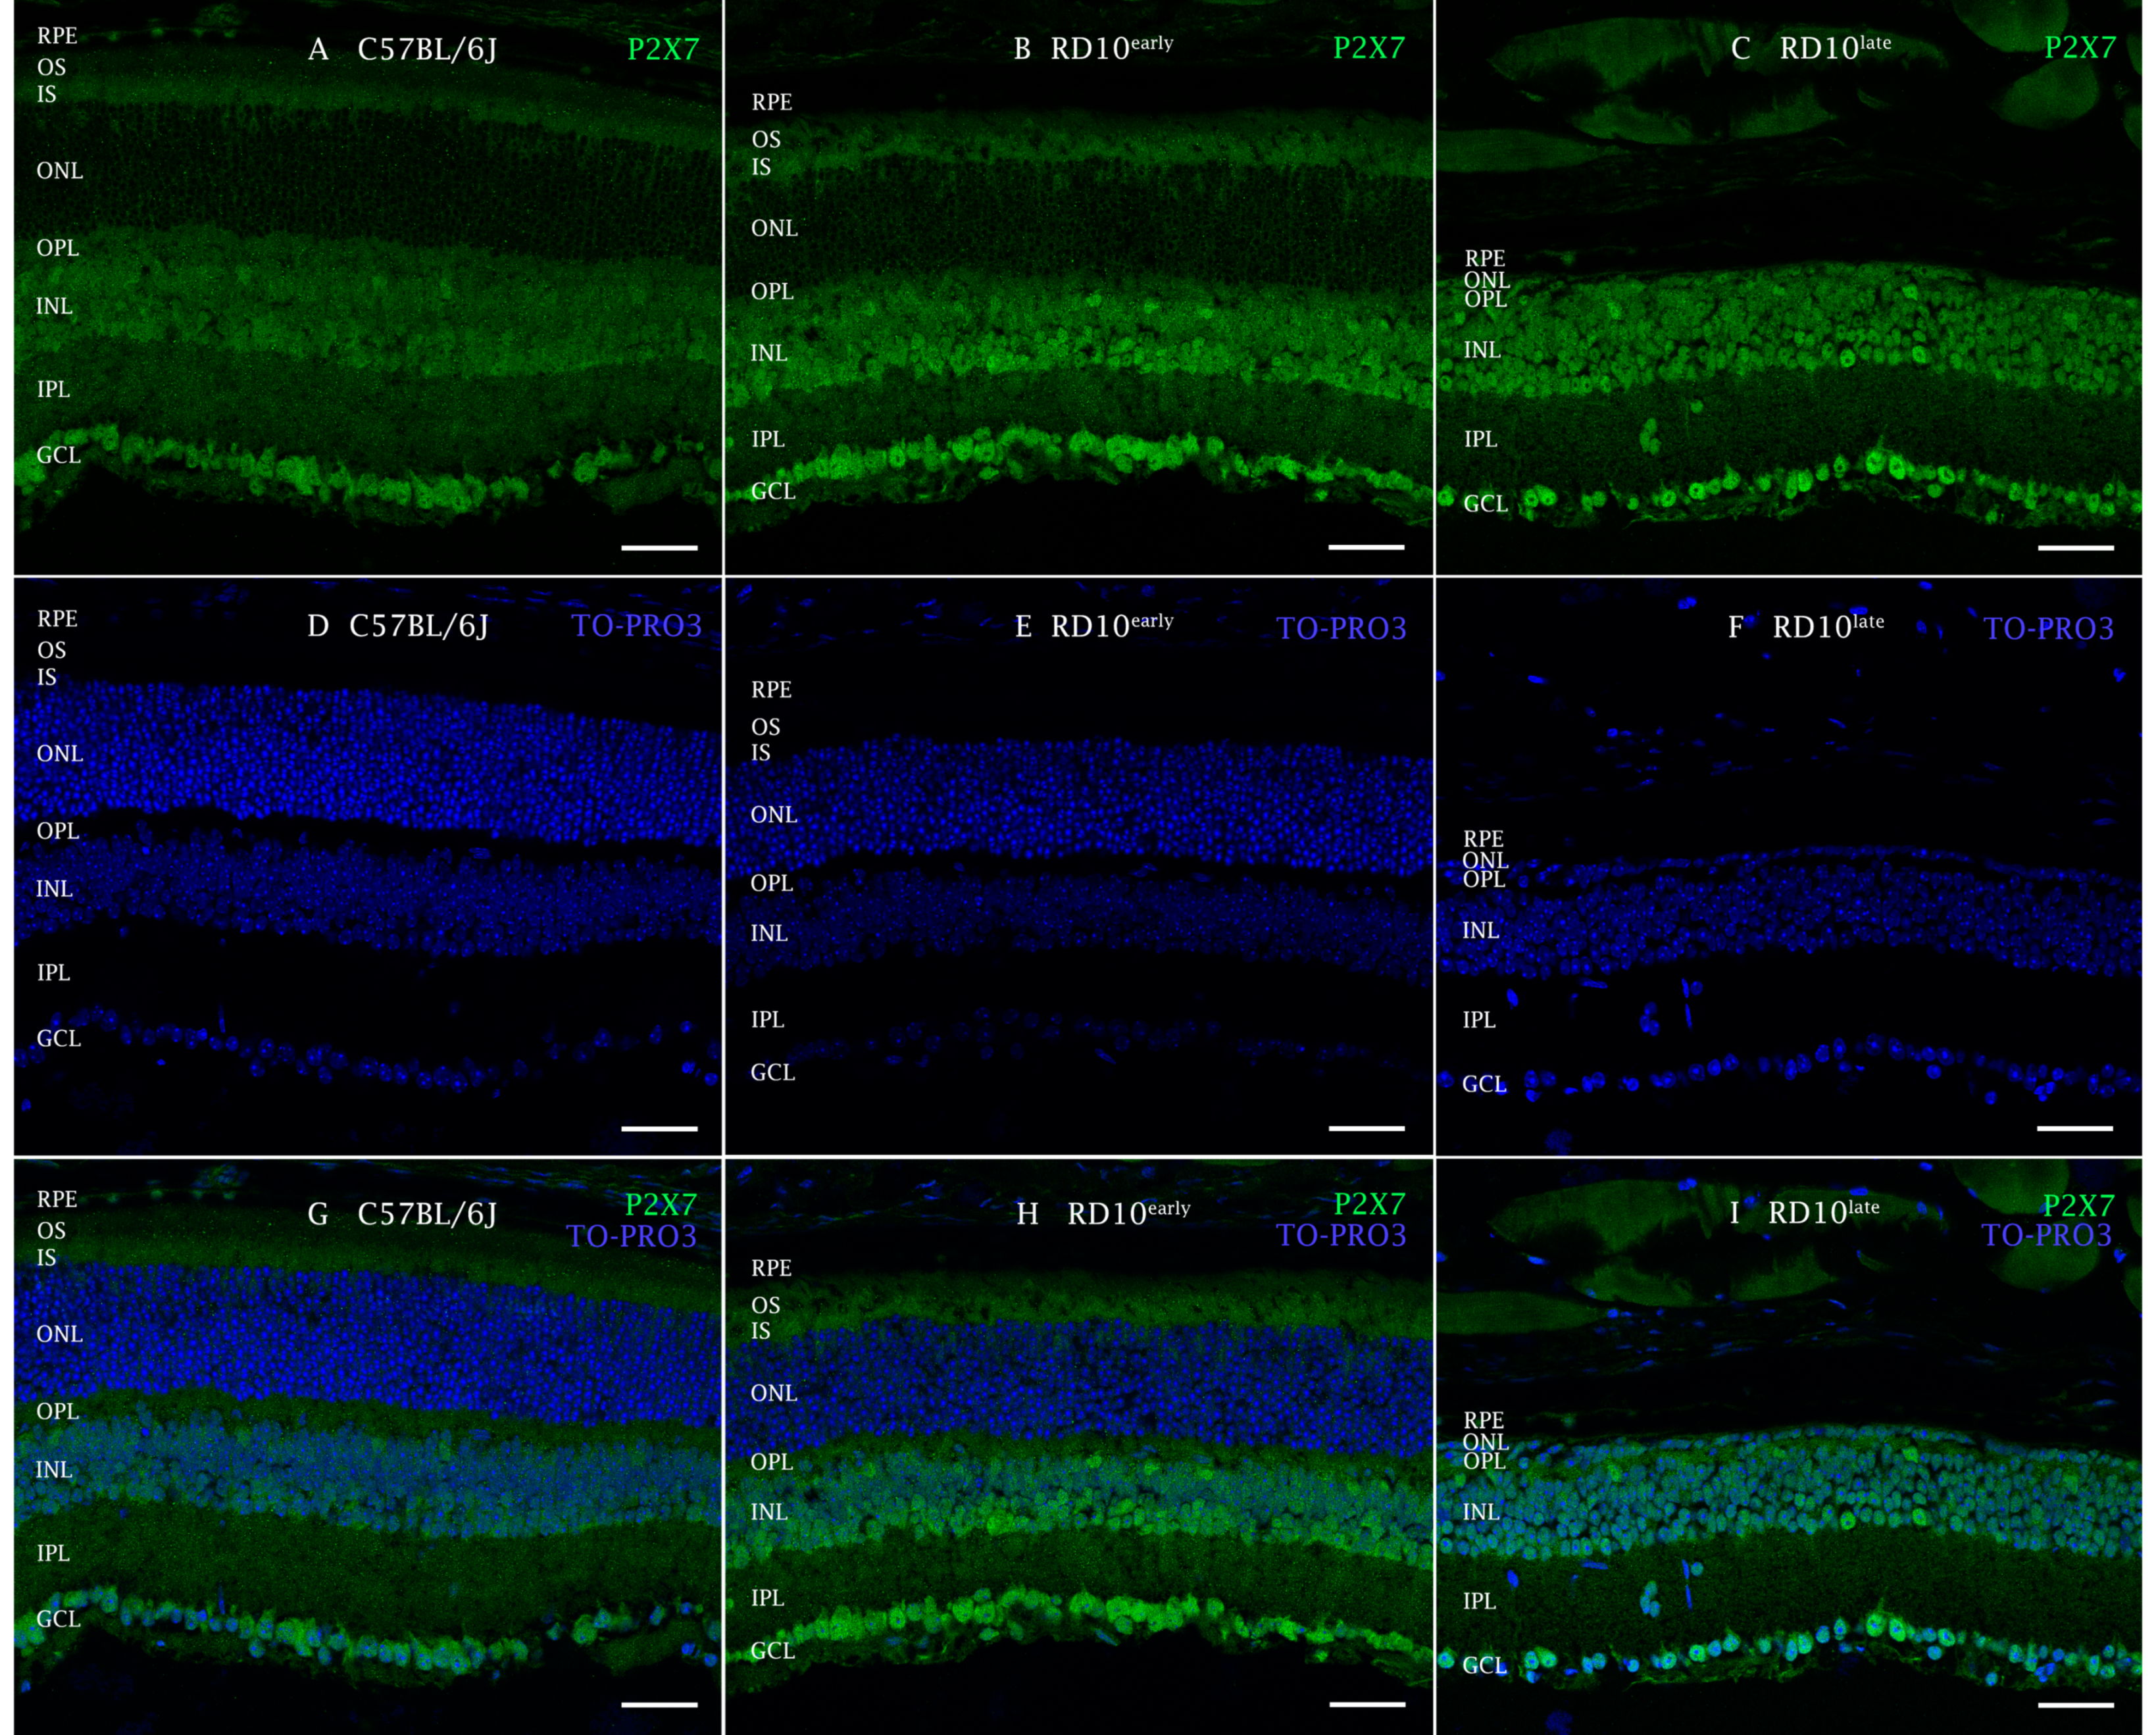

2.2. P2X7R Expression in rd10 Mice